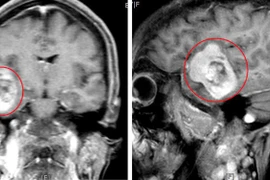

Đau đầu bất ngờ phát hiện u màng não khổng lồ ăn sâu vào não

Đau đầu, bất ngờ phát hiện u màng não khổng lồ ăn sâu vào não

Chưa hề phát hiện bệnh lý về sọ não, đau đầu nhiều uống thuốc không đỡ, bệnh nhân bất ngờ phát hiện u não 50mmx 70mm. Phải 8 tiếng các bác sĩ mới lấy được khối u phát triển sâu vào tổ chức não.